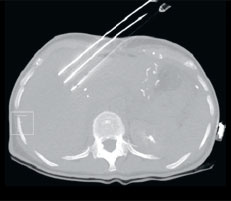

Abb. 1

Mehrere Metastasen in beiden Leberlappen. Die nahe an einem ­Blutgefäss gelegene Metastase im linken Leberlappen wird mit dem IRE-Verfahren behandelt. Zunächst werden mehrere Sonden in ­paralleler Anordnung in den Au­ssenbereich der Metastase unter CT-Kontrolle vorgeschoben.

Abb. 1a

Positionierung der IRE-Sonden in CT-Ansicht.

Das IRE-Verfahren kann entweder intraoperativ oder bildgesteuert durch die geschlossene Bauchdecke erfolgen. In diesem Fall ist die Bildgebung zur korrekten Platzierung der Sonden essenziell, um den Tumor oder die Metastase genau zu lokalisieren. Sie erfolgt in der Regel mittels Computertomographie. Im Fall von Frau O. wurde eine Behandlung durch die Bauchdecke gewählt. Mehrere Sonden in Form von langen Nadeln werden um die Metastase herum platziert (Abb. 1). Dabei ist wichtig, dass die Sonden parallel und in regelmässigen Abständen an den Aussenbereichen des Zielvolumens angeordnet werden (Abb. 1a). Sie werden dann an einen Generator angeschlossen, der abwechselnd jeweils zwischen zwei Nadeln elektrische Spannungen aufbaut. Die Ausdehnung des verödeten Volumens wird in Echtzeit berechnet und kann vom Bediener jederzeit überprüft und korrigiert werden.